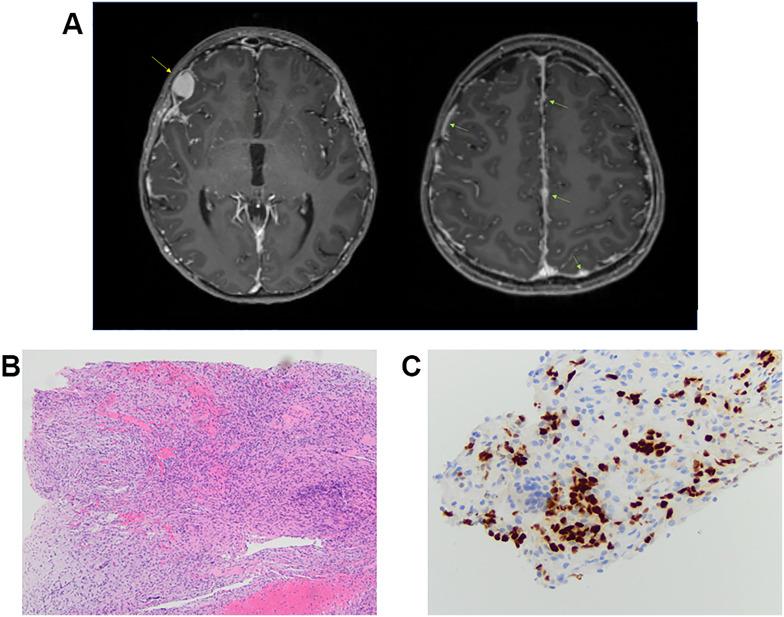

Through the implementation of paired analysis, this study identified 4 of 314 (1.3%) individuals who harbored a germline variant associated with NS, of which 3 individuals were diagnosed with a glioma or glioneuronal tumor. Furthermore, we extend this study through collaboration with a peer institution to identify two additional individuals with NS and a glioma or glioneuronal tumor. Notably, in three of five (60%) individuals, paired genomic profiling led to a previously unrecognized diagnosis of Noonan syndrome despite an average age of cancer diagnosis of 16.8 years. The study of the disease-involved tissue identified signaling pathway dysregulation through somatic alteration of genes involved in cellular proliferation, survival, and differentiation.

Comparative pathologic findings are presented to enable an in-depth examination of disease characteristics. This comprehensive analysis highlights the association of gliomas and glioneuronal tumors with RASopathies and the potential therapeutic challenges and importantly demonstrates the utility of genomic profiling for the identification of germline cancer predisposition.